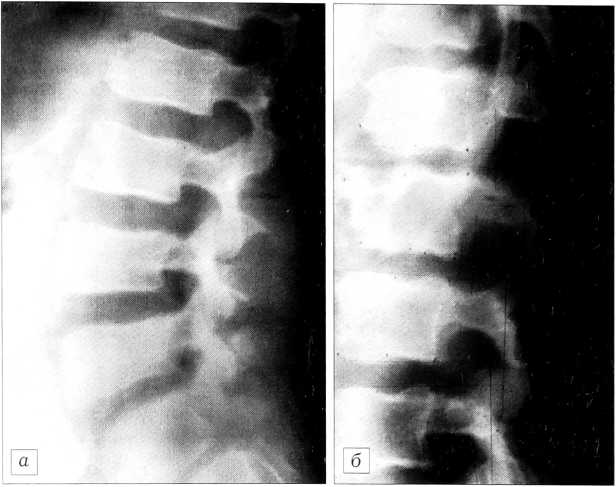

Значительно реже (всего у 16 больных — 6,4%) встречались аксиально вытянутые тела позвонков: их вертикальный размер превышал диаметр, а высота смежных межпозвонковых дисков была увеличена (рис. 1).

Рис. 1. Диспластическая деформация тел L3, L4 позвонков (аксиально вытянутые тела).